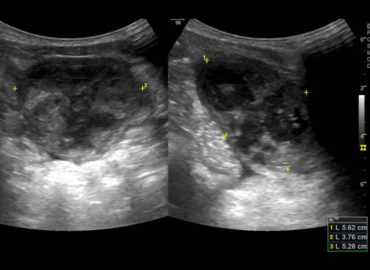

Niño de 3 años, sin antecedentes previos. Motivo de consulta: fiebre y disuria de 5 días de evolución Ecografía renovesical […]